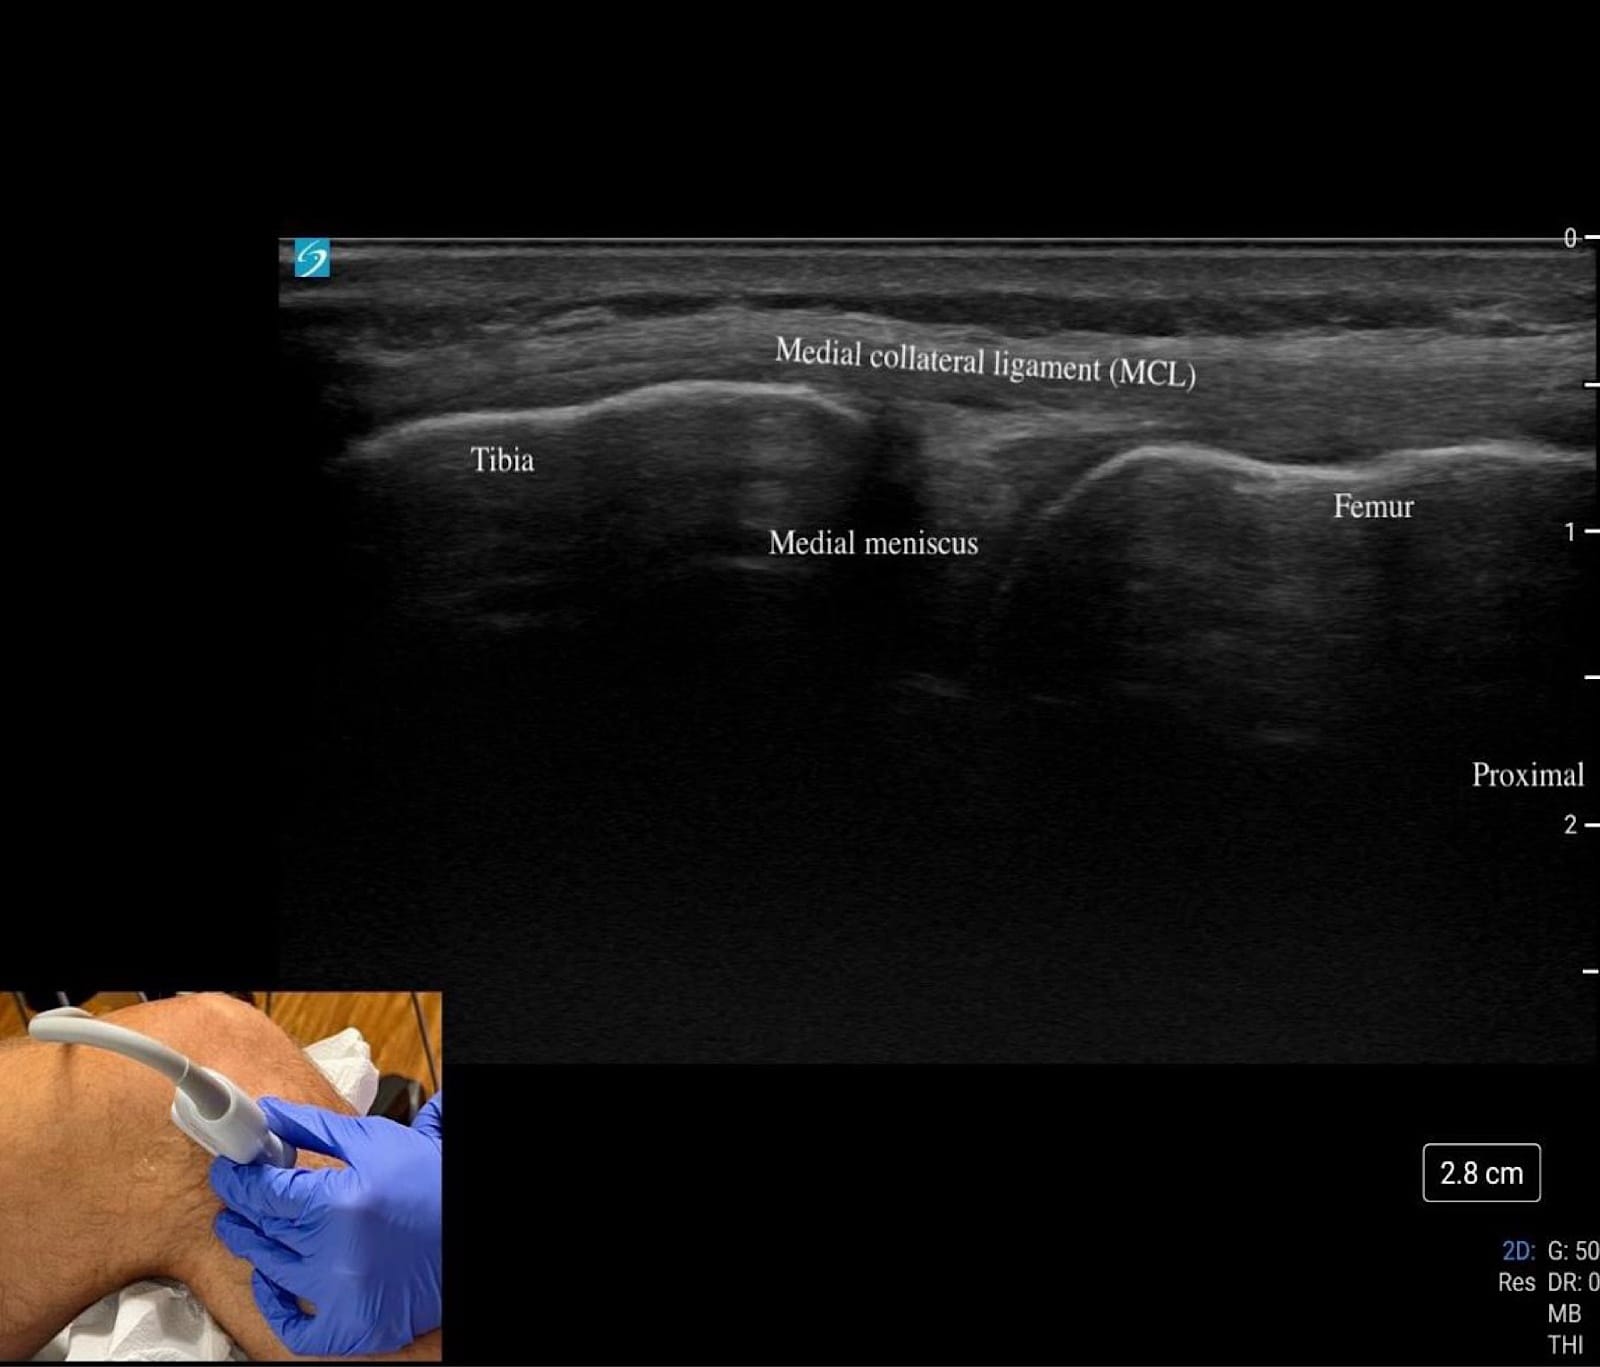

Medial Knee

Begin at “home base” by palpating the adductor tubercle on the femur and placing the transducer in long axis over this landmark, scanning distally toward the medial joint line to evaluate the MCL, which inserts proximally at the tubercle and distally on the tibia (refer to figure 2). The MCL should appear as a thin, homogeneous, hypoechoic to mildly hyperechoic, fibrillar band (refer to figure 6C); dynamic valgus stress at 20–30° flexion can help demonstrate fiber laxity or discontinuity in cases of a sprain or tear.

At the medial joint line, identify the femur superiorly and tibia inferiorly as bony landmarks. Sweep posteriorly and anteriorly along the joint line to assess the medial meniscus, looking for hypoechoic clefts, adjacent fluid, or parameniscal cysts suggestive of tear or extrusion (refer to Figure 6C).

Key Structures: Medial collateral ligament (MCL), medial meniscus, pes anserine tendons/bursa (Figures 6A-C).